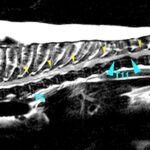

<症例情報> 雑種猫 14歳 去勢済みの男の子 主訴:後ろ足を引きずっていることで来院神経の検査では後ろ足の麻痺を認め、左よりも右後ろ足の麻痺がより強…